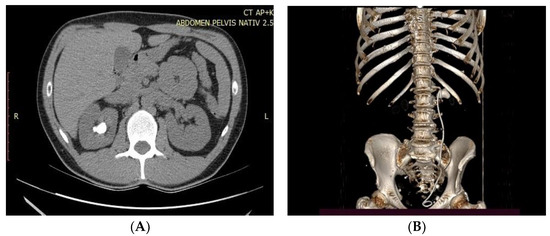

We retrospectively analyzed 250 consecutive patients with large renal solitary stones (stone burden between 2 and 4 cm) from 1 January 2019 to 31 December 2020. The patients were divided into two groups: group 1 (125 patients), in which the patients were treated by a retrograde flexible ureteroscopic approach, and group 2 (125 patients), in which patients were treated by percutaneous nephrolithotomy. Stone characteristics and anatomical data were observed based on the computed tomography (CT) and/or KUBradiography imaging archive. For larger stones, more than one session of flexible ureteroscopy was necessary. The preoperative CT images calculated the stone surface area based on the largest volume (length × width  =  mm2). The follow-up evaluation was undertaken one month after the operation using plain film of KUB(Kidney-ureter-Bladder) for opaque stones, ultrasonography for non-opaque stones, or non-contrast CT of the whole abdomen (Figure 1A,B).

Figure 1. (A,B). CT scan image and reconstruction of large pelvic stone.